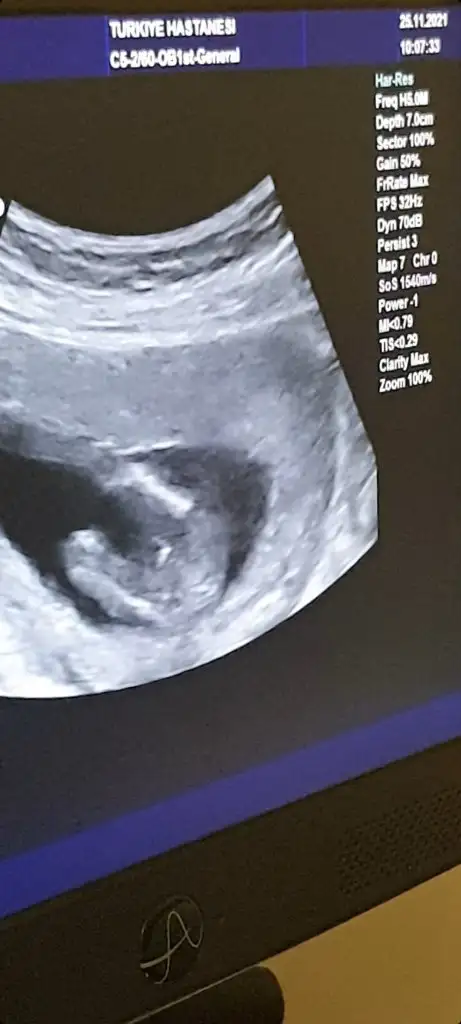

Erkek ve kız için 11 + 12+ yada 13 hafta usg görüntüsü olmalı açıklamalar asagıda yazıyorrabbim herkesin gönlüne göre nasip etsin inşallah .. ecmain

[/B]Eki Görüntüle 473828 gordugunuz gibi ust taraftaki simgedende anlasildigi gibi eger cikinti paralel ise kiz

yok 30°lik bir aciyla yukari dogru bakiyorsa %99 oglunuz olacak demektir simdi bi kac ornek resimler daha koyacagim kiziminkide dahil

Eki Görüntüle 473829 bu bir erkek bebek genital nub cikintisi gayet yukarda

Eki Görüntüle 473831 simdi burada cikintilara bakin eger bel popo cizgisine paralel ise kiz

yok 30 derecelik bir aciyla yukari bakiyorsa erkek

yabancilarin hepsi biliyor bunu biz neden eksik kalalim gayet bilimsel simdi ellerinde11 12 13 ultrason fotografi olanlar alsin hemen baksin yada koyalim buraya yorumlayalim